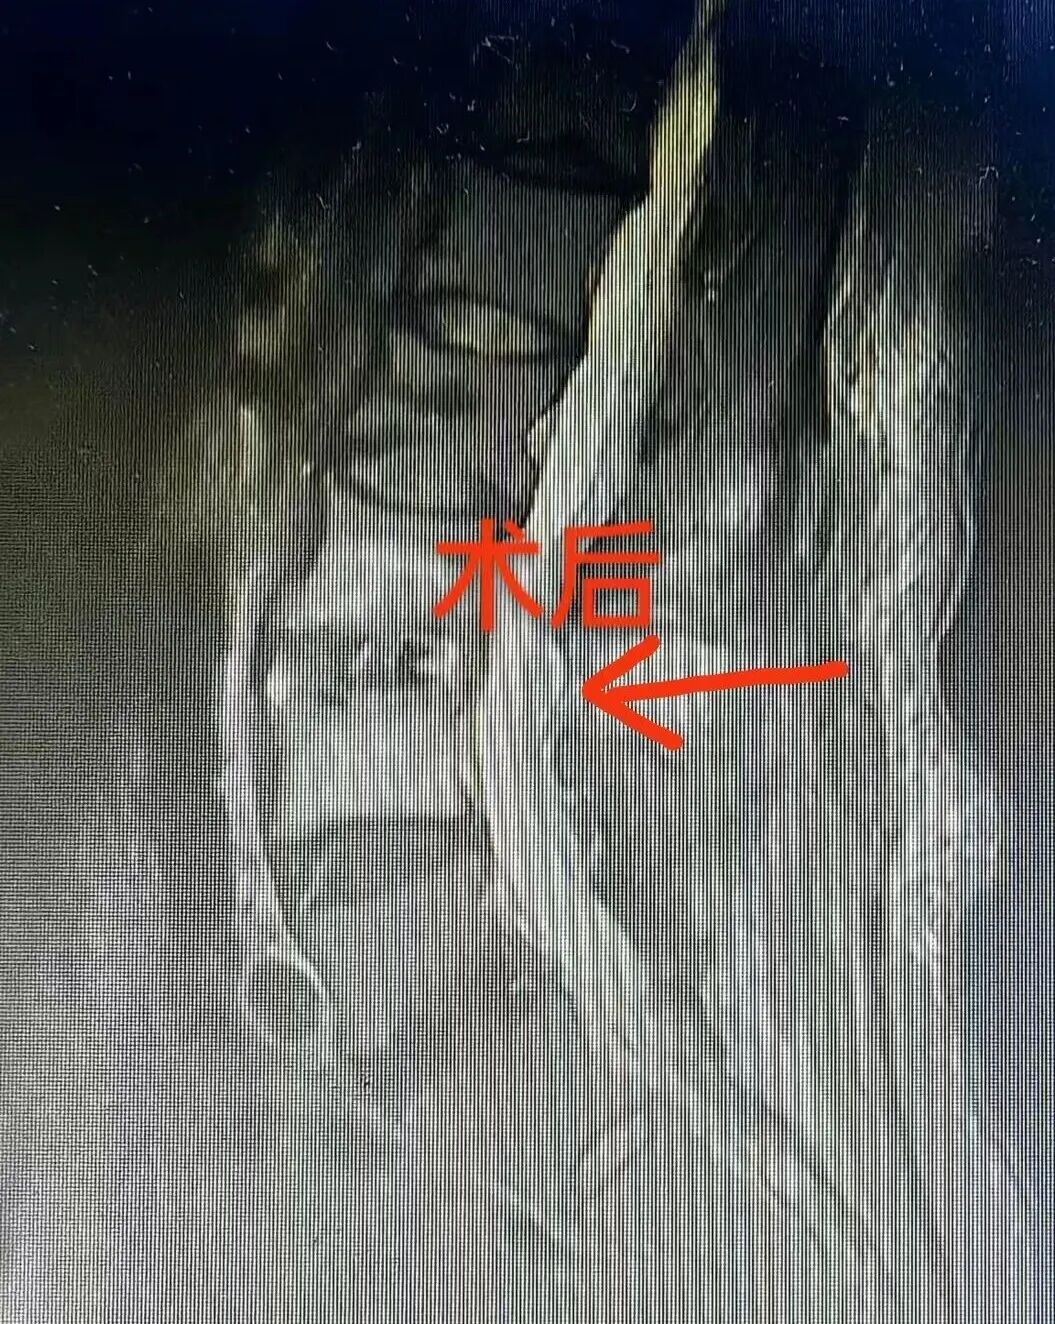

经过周密的评估与准备,手术时机成熟。由骨科团队为杨大妈精准施行了 “L3-L4椎管减压+椎间盘植骨融合+病灶清除术” 。手术成功只是第一步,术后的康复管理与专业护理同样至关重要。在骨科医护团队的精心照护与科学指导下,杨大妈的康复进程令人欣慰:

术后第二周:“终于能自己走路了,太感谢你们了!”——这句朴素的感叹,是她最真实的喜悦。